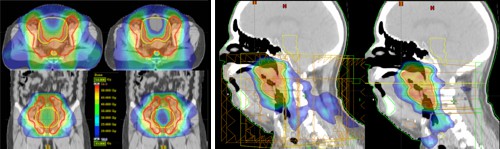

Jak plyne z předešlého, dovoluje technika IMRTIMRT – Intensity Modulated Radiotherapy, radioterapie s modulovanou intenzitou svazku. lepší pokrytí cílového objemu při současném šetření důležitých orgánů ležících v jeho těsné blízkosti, než umožňuje CRTCRT – Conformal RadioTherapy, radioterapie s přesným vymezením ozařovacího pole na oblast nádorového ložiska, prostřednictvím mnohalistového kolimátoru (MultiLeaf Colimator).. Na obr. 12 je dvakrát stejný CT řez pánevní oblastí pacienta s karcinomem prostaty. V levé části vidíme ozařovací plán technikou IMRT, vpravo pak ozařovací plán klasickou technikou „box“ bez použití IMRT. Červená kontura uprostřed označuje cílový objem, který je potřeba pokrýt minimálně 95% izodózouIzodóza – plocha v prostoru, kterou charakterizuje všude stejná velikost absorbované dávky, popřípadě dávkového příkonu.. Kruhový útvar v dolní části je rektum, modře konturovaný objekt ve střední části spíše nahoře, představuje močový měchýř. V obou případech se jedná o kritické orgány, neboť jsou relativně radiosenzitivní a leží v těsné blízkosti ozařovaného cílového objemu. Teplejší barvy značí vyšší absorbovanou dávku. Je dobře patrné, kterak se technika IMRT mistrně vyhýbá rektu, zatímco technika „box“ jej zasahuje minimálně ze 2/3 plnou dávkou. Rovněž procentuální ozáření objemu močového měchýře vychází u techniky IMTR o něco příznivěji.

Obr. 12: Srovnání IMRT (vlevo) a CRT (vpravo)

ozařovacích plánů radioterapie prostaty

Obr. 13: Srovnání ozařovacích plánů IMRT (vlevo) a RapidArc (vpravo) radioterapie. Je dobře patrné, že obě dvě metody dokážou velmi kvalitně pokrýt nádorové ložisko, avšak metoda RapidArc je ještě šetrnější k okolním zdravým tkáním..